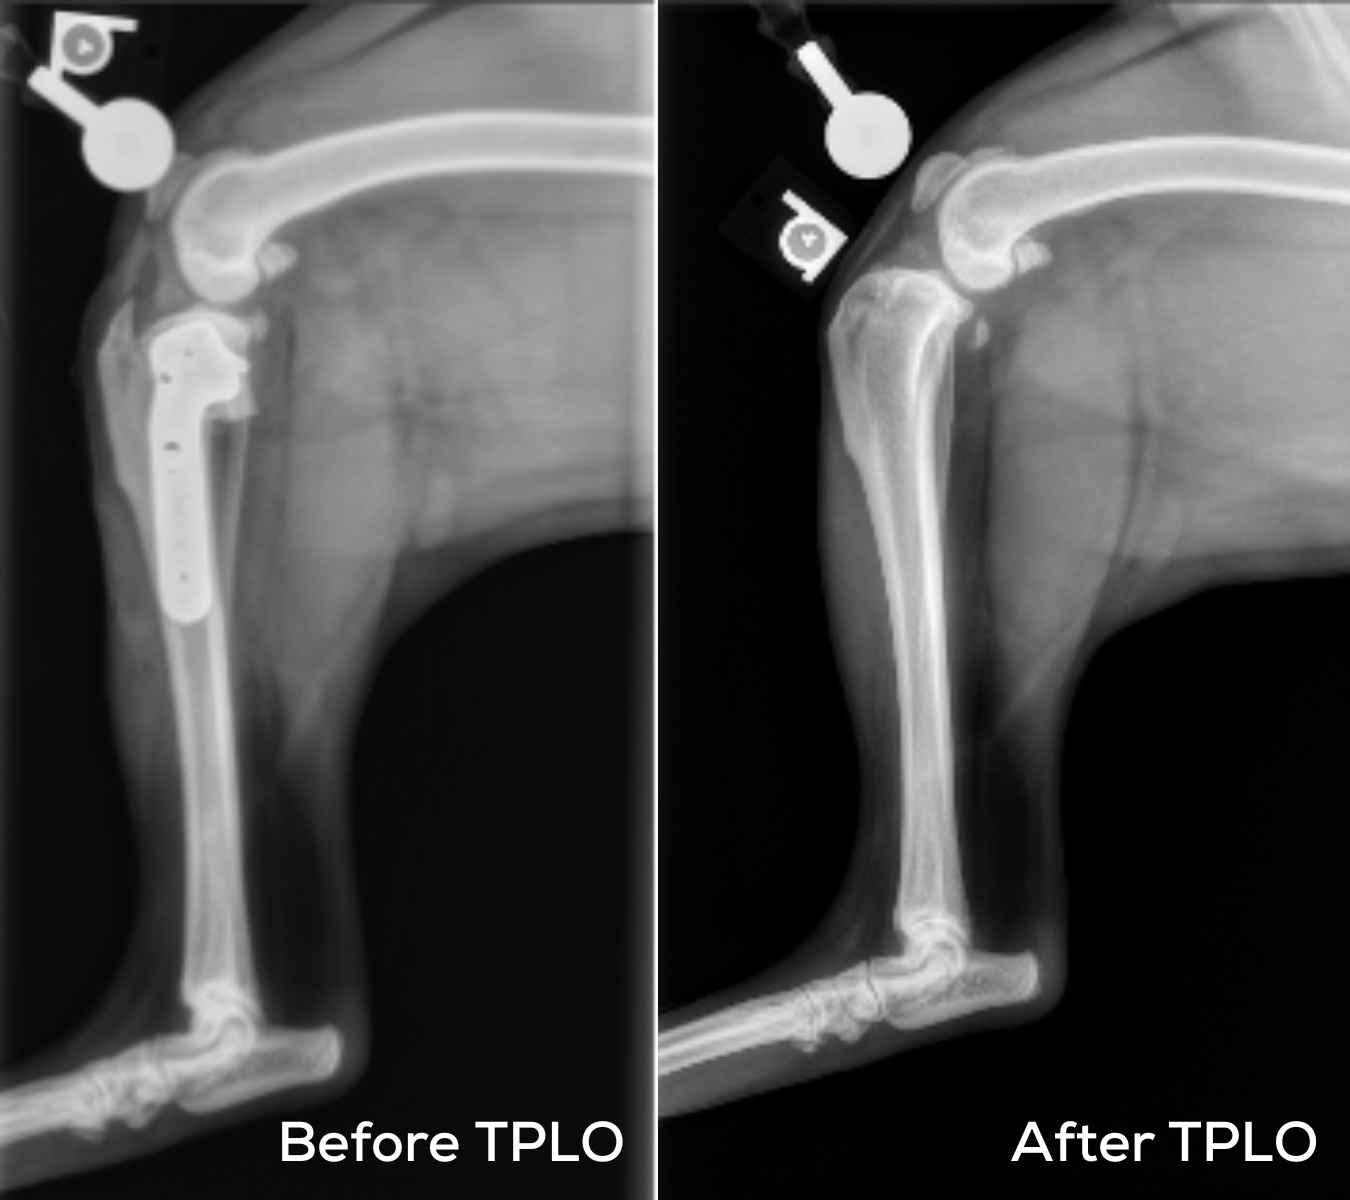

The procedure involves cutting and rotating the tibial plateau to change the slope of the knee joint. A metal plate and screws are used to secure the new angle, allowing for stable movement and healing.